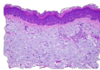

Histologic characteristics of allergic skin disease

Lymphocyte and eosinophillic dermatitis

Scale